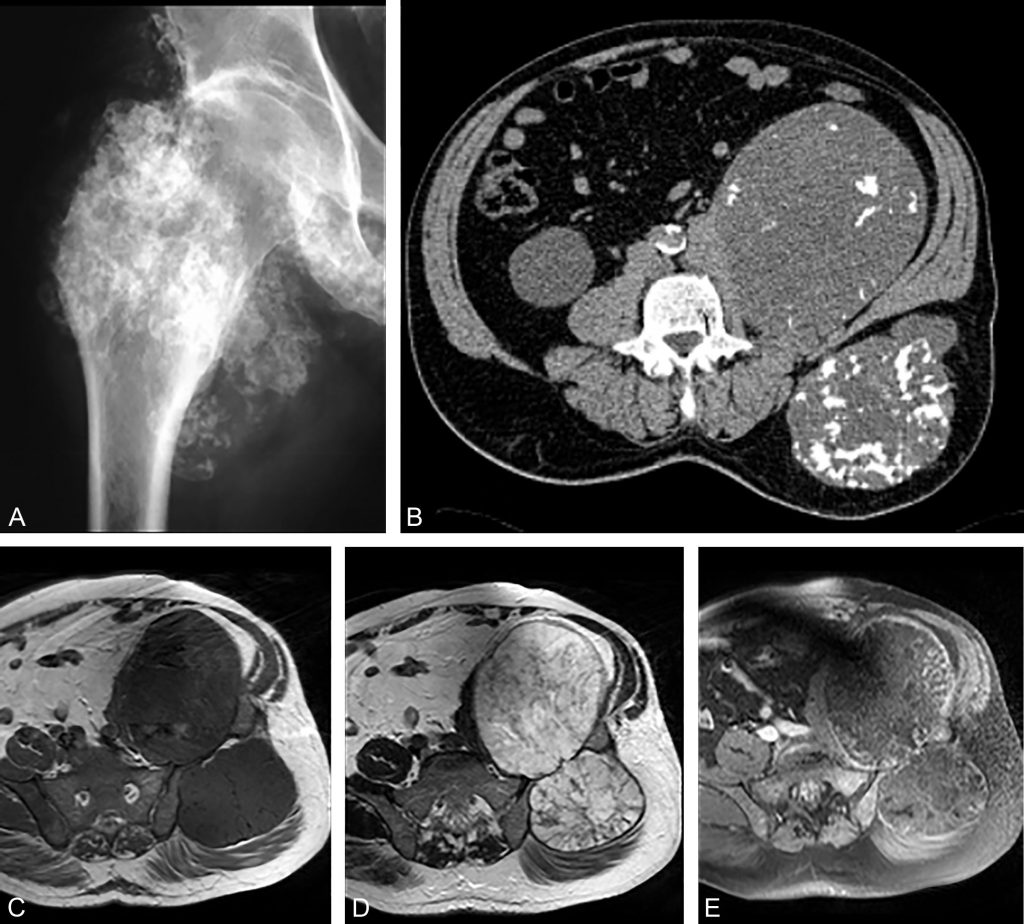

Fig. 87.2 Chondrosarcome de l’aile iliaque gauche.

La matrice cartilagineuse est évoquée devant des calcifications arciformes visibles sur la radiographie (A) et le scanner (B) ainsi que sur l’IRM en hyposignal T1 (C), hypersignal T2 (D) avec un rehaussement en arc et anneaux sur la séquence T1 Fat Sat après injection de produit de contraste (E). Notez l’extension de la lésion aux parties molles endo- et exopelviennes.

Source : CERF, CNEBMN, 2022.